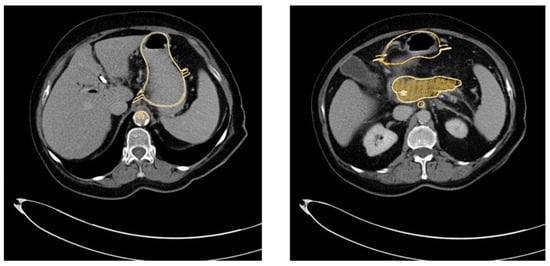

Our 3D-printed replica of the pancreatic tumor and its surroundings mirrored the real-life situation in patients very closely, as evaluated by three different endoscopists. The CT scan of the 3D-printed replica proved the high congruency between the model and the original patients’ data (Figure 9).

Figure 9.

Overlay of the CT scan and the 3D-printed model (golden) and the original patient’s CT scan, demonstrating the high congruency between the replica and the original data.